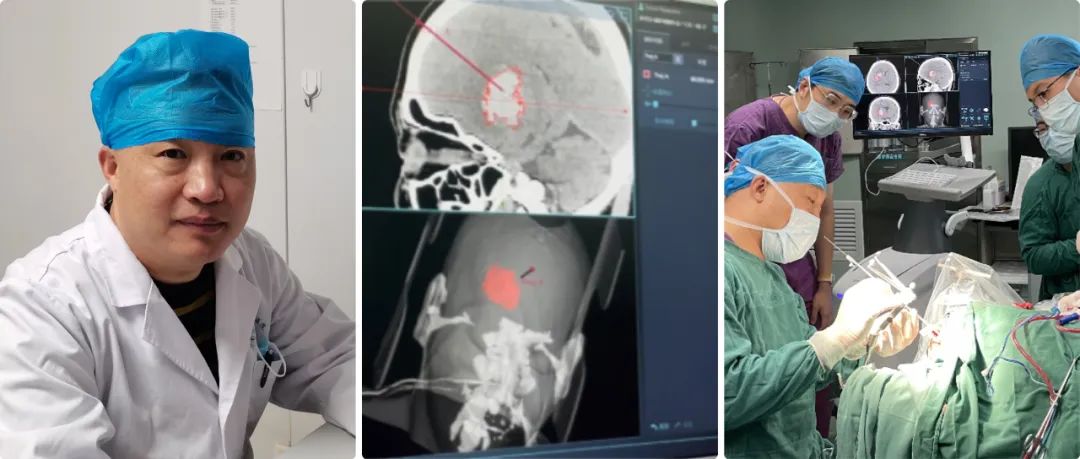

濟(jì)南市濟(jì)陽(yáng)區(qū)人民醫(yī)院高磊:神經(jīng)導(dǎo)航讓基層神外科室水平躍升 惠及區(qū)域及周邊患者

高磊:我院神經(jīng)外科自1998年正式成立,至今經(jīng)過二十余年的努力,已成為濟(jì)南市濟(jì)陽(yáng)區(qū)人民醫(yī)院發(fā)展最為迅猛的學(xué)科之一。科室開放床位45張,其中搶救、監(jiān)護(hù)床位5張。年門診量5000余人次,年收治患者2600余人次,每年完成各類手術(shù)400余臺(tái),其中危重的病人手術(shù)170-200例左右。

高磊:濟(jì)陽(yáng)區(qū)人口約53萬左右,我們是濟(jì)南市黃河以北地區(qū)重型顱腦外傷、出血性腦血管病及其它腦科急癥救治中心,區(qū)內(nèi)腦出血危重癥基本上都到我們醫(yī)院就診;我們治療范圍也輻射了周邊縣/區(qū),但是量不大。

自從引進(jìn)導(dǎo)航系統(tǒng),我們科室技術(shù)水平得到了大幅的提升,正如剛才所講沒有導(dǎo)航之前,我們腦出血都是手術(shù)開顱,徒手穿刺誤差比較大,穿刺效果也比較差,有時(shí)病人的病程住院時(shí)間延長(zhǎng)了,而且效果也不好。

現(xiàn)在我們有了導(dǎo)航,穿刺技術(shù)可以說得到了質(zhì)的飛躍;在導(dǎo)航輔助下,基本上可以說穿刺百發(fā)百中,病人術(shù)后恢復(fù)也非常快,功能改善也非常顯著,科室技術(shù)水平得到了飛躍式的提升,區(qū)域及周邊病人的社會(huì)評(píng)價(jià)也反響很好。